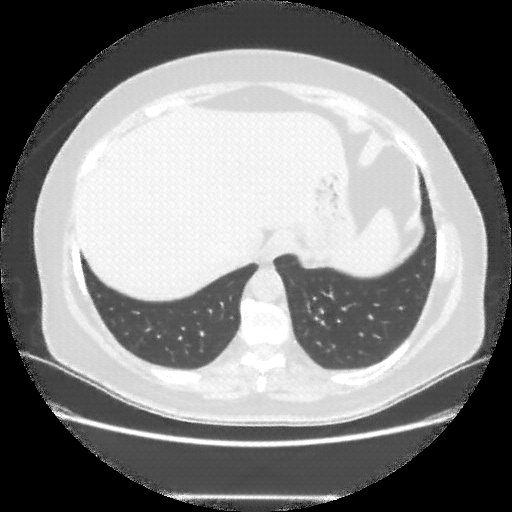

Generated VENOUS CT scan (A→B translation)

No window - Raw intensity values

Lung window (WL -600, WW 1500 β†’ Low βˆ’1350, High +150)

Mediastinum window (WL 40, WW 400 β†’ Low βˆ’160, High +240)